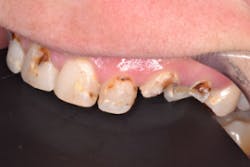

Wednesday is sedation day in our office, It's one of my favorite days—one patient and all the time I want to care for that one person. Using 3.5x loupes, caries detecting solution, and slow-speed excavation, we teased out massive amounts of decay throughout the arch with complete pulpal communication in teeth Nos. 6, 10, and 11 (figure 4). We were prepared for pulpal involvement and the possibility that multiple teeth might require root canal treatment on the fly. I immediately performed same-day root canals on the three teeth (figure 5).

All that remained of the patient's decayed teeth were "stubs and nubs" emerging from nonbleeding healthy gingiva. I cleaned the teeth, total-etched with Ultra-Etch (Ultradent), applied All-Bond (Bisco), and thinned and cured.